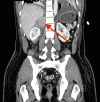

A previously well 34-year-old man presents with electrical storm after performing headstands. A step-by-step review of clinical information and case development is presented with discussion. Ultimately, 2 rare diagnoses are discovered and their potential contribution to a cascade of complications resulting in ventricular arrhythmia are discussed. (Level of Difficulty: Intermediate.).

Keywords: congenital heart disease; pheochromocytoma; ventricular tachycardia.